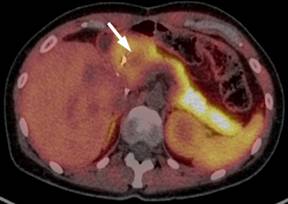

On the following abdominal CT scans performed between 90 and 95 months of follow-up, gradual enlargement of the pancreatic head with the suspicion of a tumor was noted (Figure 4). This was confirmed by both endoscopic ultrasound (Figure 5) and 11C-acetate PET/CT scan (Figure 6). Moreover, microscopic examination of the fine-needle aspirate of the pancreatic head tumor obtained during endoscopic ultrasound showed the presence of atypical hepatocytes within the tumor. In view of this, the patient was accepted for surgical treatment again and pancreaticoduodenectomy with the �uncut Roux� reconstruction was successfully performed at 97 months since the initial surgery. The pathologic examination revealed the diagnosis of a metastatic fibrolamellar hepatocellular carcinoma of the head of the pancreas. The postoperative course was uneventful and the patient did not experience recurrence within the last 18 months after pancreaticoduodenectomy. Following five laparotomies and one thoracotomy for fibrolamellar hepatocellular carcinoma and its recurrences, the patients remains well at the overall follow-up of 114 months at present.

|

Figure 6. 11C-acetate PET/CT scan showing a decreased uptake of the tracer within the pancreatic head (arrow) as compared to the remaining pancreatic tissue suggesting the presence of a pancreatic head tumor. |